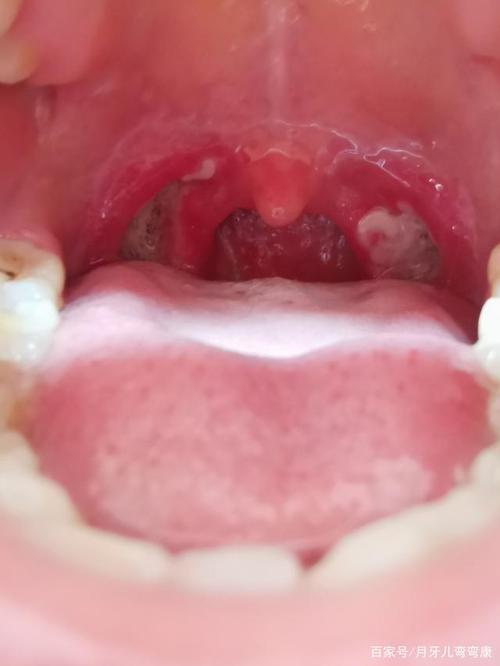

扁桃体术后白膜脱落过程图

扁桃体术后白膜

扁桃体术后图片

扁桃体术后恢复照片

扁桃体术后恢复过程图

扁桃体手术后痊愈图片

扁桃体手术伤口白膜图

扁桃体手术伤口恢复图